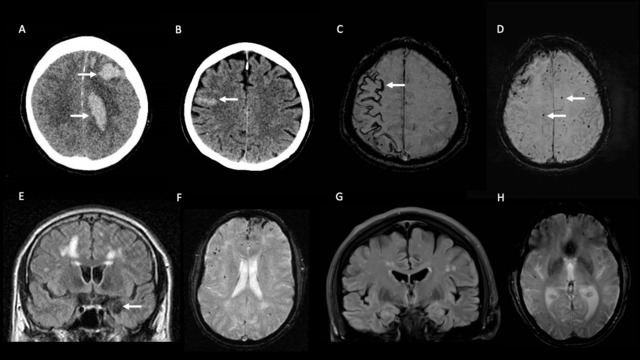

Cerebral amyloid angiopathy (CAA) is an important cerebral small vessel disease associated with brain haemorrhage and cognitive change. The commonest form, sporadic amyloid-beta CAA, usually affects people in mid- to later life. However, early-onset forms, though uncommon, are increasingly recognised and may result from genetic or iatrogenic causes that warrant specific and focussed investigation and management. In this review, we firstly describe the causes of early-onset CAA, including monogenic causes of amyloid-beta CAA (APP missense mutations and copy number variants; mutations of PSEN1 and PSEN2) and non-amyloid-beta CAA (associated with ITM2B, CST3, GSN, PRNP and TTR mutations), and other unusual sporadic and acquired causes including the newly-recognised iatrogenic subtype. We then provide a structured approach for investigating early-onset CAA, and highlight important management considerations. Improving awareness of these unusual forms of CAA amongst healthcare professionals is essential for facilitating their prompt diagnosis, and an understanding of their underlying pathophysiology may have implications for more common, late-onset, forms of the disease.